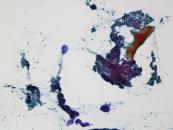

第38回日本臨床細胞学会九州連合会学会(熊本)スライドカンファレンス症例3

種別:消化器・口腔

出題:甲斐 敬太 佐賀大学医学部附属病院病理部

| 年齢 | 60代 | 性別 | 男性 |

| 採取部位 | 胆汁 | 採取方法 | 経皮経肝胆道ドレナージ |

既往歴:潰瘍性大腸炎治療中。

現病歴:難治性の十二指腸潰瘍を合併し、通過障害をきたしていた。閉塞性黄疸が出現し、精査で原発性硬化性

胆管炎が疑われた。減黄目的に経皮経肝胆道ドレナージが行われ、胆汁が提出された。なお、狭窄部の

胆管と十二指腸潰瘍部から生検が行われたが、悪性所見は指摘できなかった。

| 正解 | 5.腺癌 |

▼選択肢及び投票結果

| 1.急性胆管炎 (反応性異型) | 1件 | (1.0%) | |

| 2.原発性硬化性胆管炎 (反応性異型) | 25件 | (24.0%) | |

| 3.Low-grade BilIN | 31件 | (29.8%) | |

| 4.Low-grade IPNB | 19件 | (18.3%) | |

| 5.腺癌 | 28件 | (26.9%) | |

| 投票総数 | 104件 | (100%) |